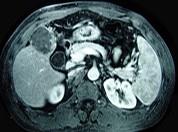

问题 男性,60岁,右上腹胀不适,右肝区叩击痛,影像检查如图,最可能的诊断是 ( )

选项 A、肝硬化、膈下脓肿 B、肝硬化、结节性增生 C、肝硬化、再生性肝癌 D、肝硬化、腹腔间质瘤 E、肝硬化

答案 C